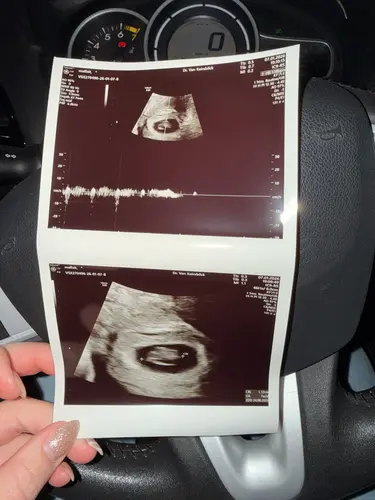

12 weken 🩵🩷 Op het bovenste beeld zie je een handje 😍